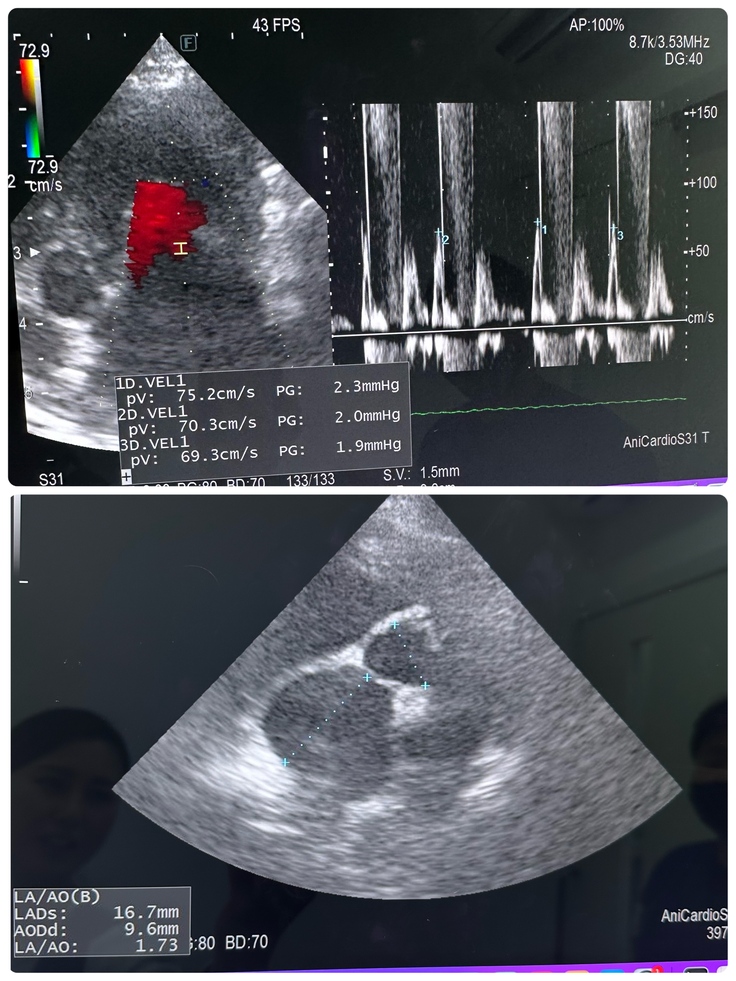

昨年10月より利尿剤の量が増え、そこから状態が安定していて、11月にレントゲンを撮って以来久々のレントゲンでした!(エコーは毎月行ってました🙌)結果、利尿剤が効いてくれているおかげで、心臓が少し小さくなってくれてました😣✨

今の薬の量が合っているおかげで他の数値も大幅に下がってました😭

特に心臓内の血液の逆流量を表すE波は病気になっていない通常の状態の平均値は(正常<0.9m/sec)なんですが、クレアは安定するまで常に1m〜1.2m/secでいつ肺水腫になってもおかしくない、もしくは少し肺水腫の状態でしたが、今日は0.75m/secと大変安定しています😭✨

その他も病気を発症時2.4あった左心房の大きさも今日は1.73と小さくなってました🥲✨

また、利尿剤を服用すると腎臓に負担がかかるため、腎臓のチェックも行なっているのですが、今のところ問題なし。本当に一先ず安心です 泣